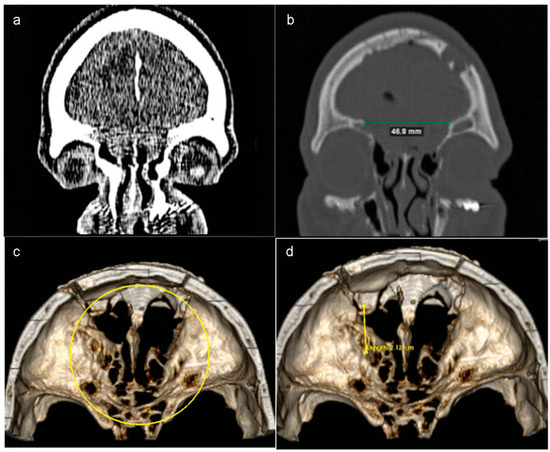

Figure 5. (a and b) Eighteen days after the procedure, the patient returned and a new CT scan revealed a large encephalocele. The protrusion of the brain through the nasal cavity was associated with an extensive defect of the anterior skull base. (c and d) Three-dimensional volume rendering images showed that the osseous defect had increased after first surgery.

After 18 days, the same patient returned with pulsatile headache, dizziness, and nausea. Besides this clinical sign, a new CT scan revealed a large encephalocele associated with an extensive defect of the anterior skull base (Figure 5a–d).